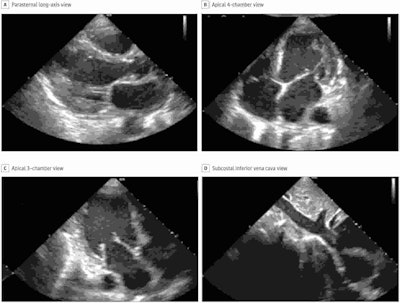

In the prospective study of 240 patients at academic medical centers, nurses were able to acquire images of high quality using a commercially available software application (Caption Guidance, Caption Health) installed on a portable ultrasound system. Images were judged to be of diagnostic quality on four key endpoints: quality for ventricular size, assessment of left ventricular size and function, right ventricular size and function, and presence of pericardial effusion.

Each nurse performed 30 scans with using the guidance software installed on a portable ultrasound scanner (uSmart 3200t Plus, Terason). The mean acquisition time was 30 minutes. Ten standard transthoracic echocardiography views were obtained for each patient.

Per the FDA, the software needed to demonstrate diagnostic quality enabling diagnosis in at least 80% of patients on four key outcome measures. The nurses' scans were of diagnostic quality in from 92.5% to 98.8% of patients (see table), with no significant difference compared with scans by sonographers.

Performance of nurses was also on par with sonographers on a range of secondary endpoints. However, performance of sonographers was better than nurses when it came to determining the size of the inferior vena cava (91.5% diagnostic quality compared with 57.4%) and this is a "clear target for further algorithm development," the authors wrote.